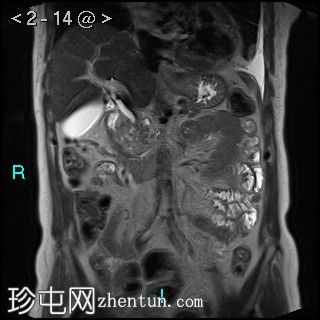

轴位

表观扩散系数 (ADC)

4.jpg

胰腺钩突附近可见边界不清的肿块,T2加权像呈不均匀中等信号,弥散受限明显。肿块大小为4.1 x 5 x 3 cm(前后径 x 横径 x 头尾径)。伴有胰管扩张,直径约6 mm。

肝脏可见多个大小不一的可疑病灶(从亚厘米级到2厘米不等)。T2加权像呈高信号,弥散受限明显。